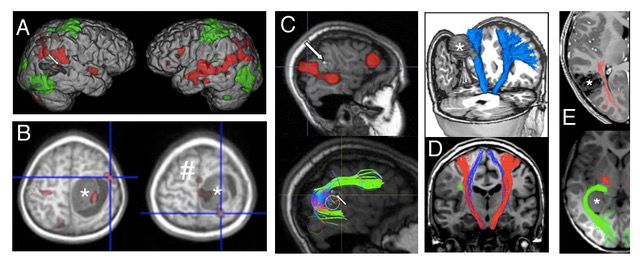

Sorgfältige und individualisierte Planung der Operation auf der Basis hochwertiger MRT Bildgebung, die je nach Lokalisation des Befundes ergänzt werden sollte durch die Darstellung von Motorik und Sprache, Darstellung relevanter Faserbahnsysteme, Charakterisierung des Stoffwechsels, Darstellung von Blutgefäßen und Hirnnerven. Vieles davon können wir dank einer spezialisierten Forschergruppe in Kinderklinik und Neuroradiologie häufig bereits für relativ kleine Kinder realisieren.